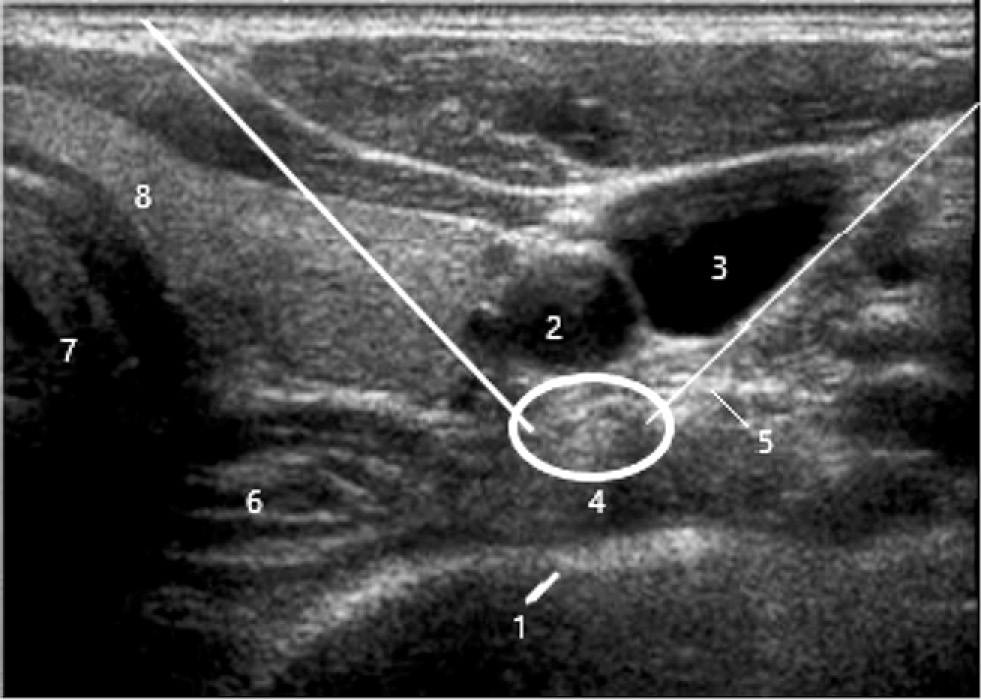

Ультрасонография (УЗИ) позволяет визуализировать ключевые структуры мягких тканей, которые дают возможность точно разместить иглу для блокады. Анатомическими ориентирами для блокады звёздчатого ганглия являются сонная артерия, длинная мышца шеи и передний бугорок шестого позвонка (бугорок Шассиньяка) [50]. В отличие от флюороскопического доступа (рис. 2), конечной точкой УЗ-доступа не является контакт с костью. Целью является плоскость между латеральной частью длинной мышцы шеи сзади и предпозвоночной фасцией, покрывающей заднюю часть оболочки сонной артерии спереди. Существуют явные различия между конечными точками иглы при флюороскопическом и УЗ-доступе, который разделён длинной мышцей шеи. УЗ-подход нацелен на переднюю поверхность мышцы (рис. 3), тогда как рентгеноскопический подход нацелен на заднюю поверхность мышцы. Кроме того, прямая визуализация сосудов и мягких тканей сводит к минимуму риск случайного укола иглой и последующей травмы при ультразвуковом контроле. Дополнительным преимуществом использования УЗИ является то, что требуется меньший объём инъекции для создания той же степени блокады, что сводит к минимуму любые необоснованные побочные эффекты введения местных анестетиков [51]. В целом под контролем УЗИ используется около 3 мл по сравнению с более чем 5 мл при рентгеноскопическом доступе.

Рис. 3. Ультразвукассистированная блокада звёздчатого ганглия на уровне C7. Белая окружность – зона блокады; 1 – гипер- эхогенная тень поперечного отростка C7; 2 – сонная артерия; 3 – ярёмная вена; 4 – длинная мышца шеи; 5 – превертебральная фасция; 6 – пищевод; 7 – трахея; 8 – правая доля щитовидной железы; белые прямые линии – направление иглы / Fig. 3. Ultrasound-assisted blockade of the stellate ganglion at the C7 level. White circle – blockade zone; 1 – hyperechoic shadow of the transverse process C7; 2 – carotid artery; 3 – jugular vein; 4 – long muscle of the neck; 5 – prevertebral fascia; 6 – esophagus; 7 – trachea; 8 – right lobe of the thyroid gland; white straight lines are the direction of the needle